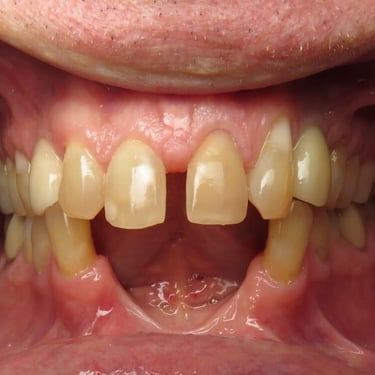

Pérdida de múltiples dientes

La pérdida de múltiples dientes es la ausencia de varios dientes que puede ser resultado de caries, enfermedades periodontales o traumatismos.

Los pacientes notan varios espacios vacíos en su boca, lo que afecta su capacidad para masticar y hablar adecuadamente.

El tratamiento incluye la colocación de varios implantes dentales para restaurar la función y la estética.